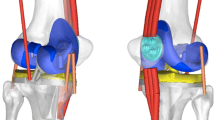

Seven fresh frozen knee specimens were tested in an isokinetic extension test in an in vitro simulation initially published by Stukenborg et al. and Ostermeier et al. [18, 20]. The Interax I.S.A.® (Stryker/Howmedica®, Ireland) was implanted into seven fresh frozen left knee cadaver (mean age 62, range 52–75 years). The knees were transected about 300 mm proximal and distal to the knee joint. The skin and subcutaneous tissues were removed, preserving the muscles, articular capsule, ligaments and tendons. The anterior cruciate ligament was removed and the posterior cruciate ligament was preserved. The Interax I.S.A.®-prosthesis-system provides a tibiofemoral articulation surface of the femoral prosthesis, which has a constant radius up to approximately 90° of knee flexion in the sagittal plane, reducing to higher degrees knee flexion degrees. The femoral component articulates on a high conforming surface with a mobile insert. The knee prosthesis permits anterior/posterior sliding and rotation of the mobile insert on the tibial base plate. Movement of the insert is guided by two metal pins on the tibial base plate which match the profile of a corresponding groove on the underside of the insert. The maximum possible movement of the insert center is 8.5 mm anterior/posterior and 18° of axial rotation relative to the tibial base plate. All specimens received the same size (400) of the femoral and tibial component. Each implantation was conducted by the same team of surgeons with the same implantation guidelines.

Insert movement and tibiofemoral position were measured by an ultrasonic tracking system (CMS 100®, Zebris GmbH, Isny, Germany), consisting of triplet markers (speakers) forming a plane for each object tracked, and a receiver unit with four microphones. The delay of the received ultrasonic signals between the microphones determined the marker position relative to the receiver unit. Each triplet marker was custom-mounted onto a PVC backing plate, forming an equilateral triangle with a base of 50 mm. One marker triangle was attached to the tibial base plate with its plane visually aligned perpendicular to the base plate horizontal plane. A second triangle was attached to the mobile bearing insert, perpendicular to the horizontal plane of the undersurface of the insert. The third triangle was fixed to the femur with unicortical screws parallel to the long axis of the femur. A distance of 1,000 mm between markers and receiver unit provided measurement of the triangle position at an accuracy of ± 0.1 mm and ±0.1° at a frequency of 10 Hz and a reproducibility of ± 0.005 mm (± 0.005°). Custom motion analysis software based on Excel® (Microsoft, USA) transformed the raw data into the anteroposterior positional coordinates of the insert center and the center of the femur relative to the center of the tibial base plate. The results were plotted as a function of flexion angle.